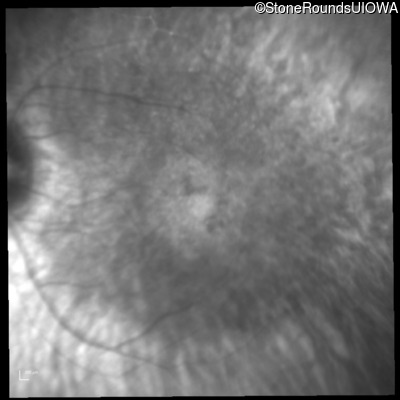

Infrared Fundus Photograph - Right - 20/80 +1

Exemplar